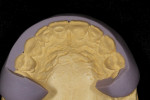

The first step in any smile design case is to create prototypes. Prototypes serve several purposes. First, they allow the patient and the dentist to preview the new smile both esthetically and functionally. Second, they show if and where any enamel reduction is needed. Third, they are used for shade communication between the patient, the dentist, and the ceramist. Prototypes can be created with bisacryl temporary material by using a diagnostic wax-up and a silicone matrix, as was done in this case (Figure 4 through Figure 7), or by hand sculpting directly in the patient’s mouth with composite. Each of these techniques has benefits and drawbacks. When the dentist fabricates the prototypes directly in the patient’s mouth they are able to get direct feedback from the patient as they are working. The laboratory technician does not have the benefit of communication with the patient or the added value of the face and lips as a guide. In cases that are extremely thin, the author has found that a bisacryl transfer will not last very long in the patients mouth due to lack of retention. Once the patient and the dentist have approved the design, an impression is taken and sent to the laboratory along with a photographic series for communication. Models are created, and platinum foil is adapted to the dies by means of tweezers, an orange wood stick, and a swager (Figure 8 through Figure 10). The laboratory technologist then fabricates a silicone matrix from the model of the prototypes to show the amount of space needed for the ceramic (Figure 11 through Figure 14). Using these tools, the ceramist is able to see how much room he has from the tooth to the final desired contour. This information is critical in determining which porcelains to use and how much opacity or translucency is needed on each individual tooth.

First, a wash bake is applied to the foil, and the foil is readapted to the die to ensure a good fit. Translucent porcelains are used in the gingival, incisal, and interproximal zones in order to blend into the natural tooth (Figure 15). Subsequent porcelain is applied and fired to achieve the desired effects and contour (Figure 16). Colored pencils and metallic paste are used to verify and establish line angles and surface anatomy (Figure 17 and Figure 18). Surface texture and final contours are reached using various rotary diamond instruments. Once the desired contour and surface morphology are achieved, the veneers are brought to a natural glaze and manually polished using a series of rubber wheels and diamond polishing paste. Finally, the foil is removed from the veneers with sharp-pointed tweezers. Because the veneers are very thin, 0.02 mm, the ceramist must be extremely careful while removing the foil (Figure 19). After the foil is removed, marginal adjustments are made with a rubber wheel. Here you can see the amount of translucency and subtle opacity built into the veneers (Figure 20). Once the veneers are placed back on the model, we can see how much they will be influenced by the underlying tooth color (Figure 21 through Figure 25). Using translucent cement, the veneers are placed immediately after bonding (Figure 26 through Figure 28).

After the prototypes were approved, the dentist took an impression and sent it to the ceramist. The ceramist created two silicone matrices (Figure 42 and Figure 43), which served as a guide for how much room there was for porcelain application (Figure 44 and Figure 45). Without this information it would be very difficult for the ceramist to plan which porcelains he would need to create the final restoration with proper translucency and color. The ceramist then fabricated the veneers with internal characterization to enhance the natural tooth (Figure 46 through Figure 49). Finally, the veneers were placed and the patient was extremely happy (Figure 50 and Figure 51).